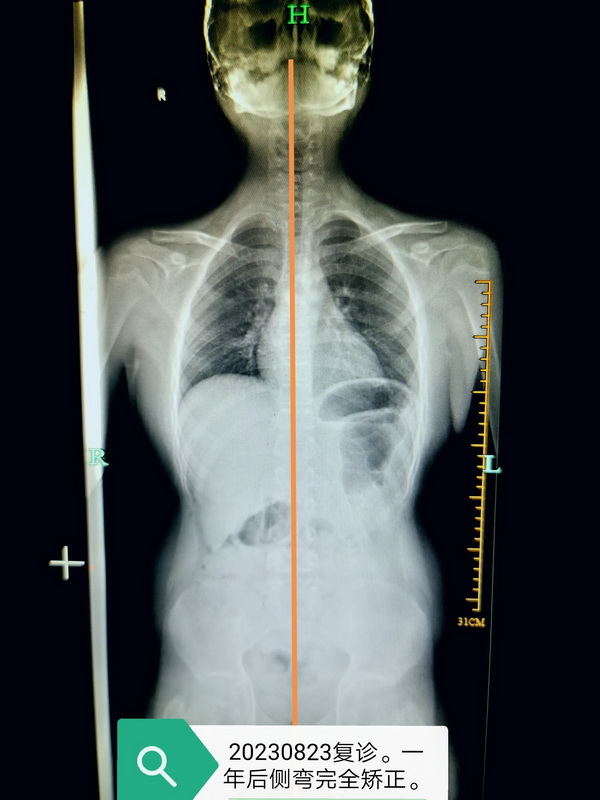

在康复运动医学科,有很多像小林一样每日坚持做矫正训练动作的孩子们,经过长期锻炼,孩子们在脊柱侧弯矫正与体态改善方面均取得显著的成果,让我们一起来看看效果吧!

矫正前VS 矫正后 矫正前VS矫正后 矫正前 VS矫正后